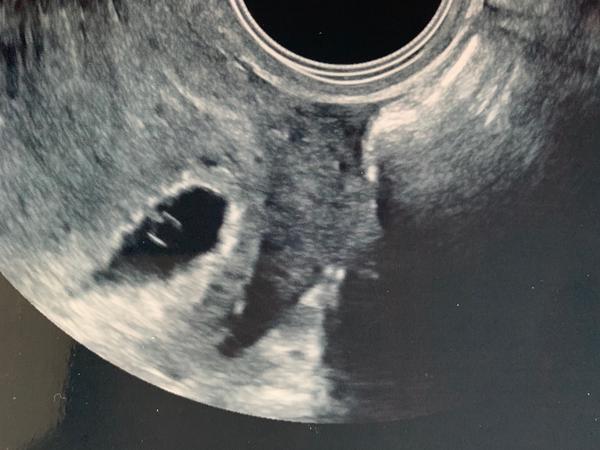

Ultrazvuk 5+5. tt. Přijde vám v pohodě?

Ahojte chcela by som sa poradiť, dnes som bola na prvom ultrazvuku v 5+5 tt ( podľa ovulácie) a pani doktorka mi k ultrazvuku nič moc nepovedala. Prikladám fotku - príde Vám v pohode ? Alebo ste videli už niečo viac na utz v 6.týždni. Vidím tam zltkovy vacok a už možno aj mimi pripojené k nemu ? Ďakujem za každú odpoveď.

Hele já myslím že je to úplně suprový , první plus je, že je to v děloze , a výsledek odpovídající , nemůžeš se řídit tím že některé holky napíši že v 5 TT měly už srdíčko , já v 6+1 neměla na utz vůbec nic a o 2 týdny později miminko odpovidalo přesně jak melo + o 5 dní starší ,,,,, takže tento utz dopadl nejlíp jak mohl , gratuluji k těhu 😉

@patricia212 Je to v pohode, ja jsem mela 5+4 jen dutinku a za mesic uz prcka se srdickem.

V 5.tt muze byt jeste brzo, aby ti neco rekla. Pockej az uvidis tlouct srdce. Proto je lepsi chodit pozdeji. Nebyla by si pak nervozni z toho co bude.